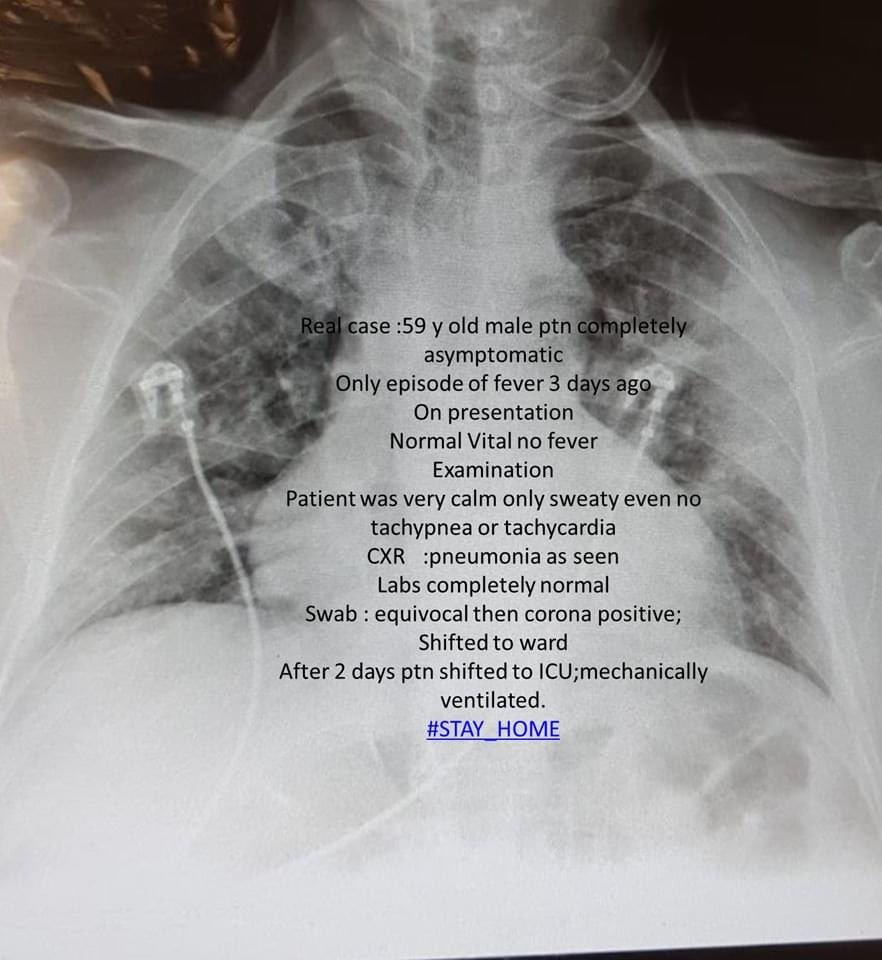

هذا القايدلاين يستخدم وقت نقل حالات ال COVID19 من الطواريء الى ال icu